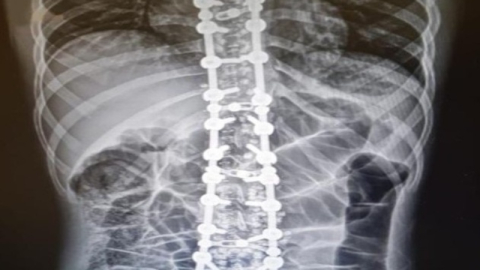

Omurganın, insan vücudunun hem destek sistemi hem de hareket merkezi olarak hayati bir rol oynadığını hatırlatan Prof. Dr. Yaman, “Modern hayatın getirileri olan uzun süreli oturma, yanlış duruş alışkanlıkları ve fiziksel aktivite eksikliği, omurganın sağlığını tehdit edebilir” dedi.